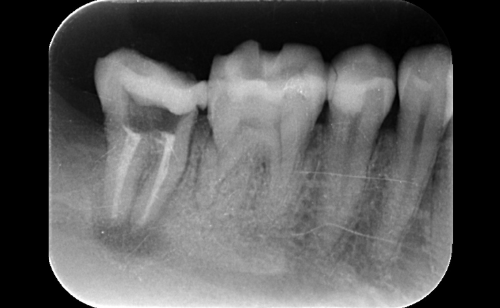

定期検診ではクリーニングのみではなく、経過観察歯のチェックや古くなってきた詰め物・被せ物のチェックなども合わせて行います。1年に1度お口全体のレントゲンをお取りさせて頂き目に見えない虫歯の確認や歯周病による骨吸収の有無をみています。

お口の中の病気はレントゲン写真検査を行わないと診断が難しいものが多くあります。直接見えない部分を把握するためにレントゲン撮影をさせて頂きます。

お口の中の病気はレントゲン写真検査を行わないと診断が難しいものが多くあります。

定期検診の場合約1〜2年に1回ほど、もしくは歯科医師・歯科衛生士の判断で必要な場合撮ることがあります。